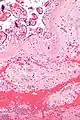

| Micrograph of a chronic deciduitis, showing the characteristic plasma cells. H&E stain. | |

Chronic deciduitis is a type of long-lasting inflammation that arises in pregnancy and affects the endometrial stromal tissue (decidua).

It is associated with preterm labour.[1] The diagnosis rests primarily on the presence of plasma cells.[2]